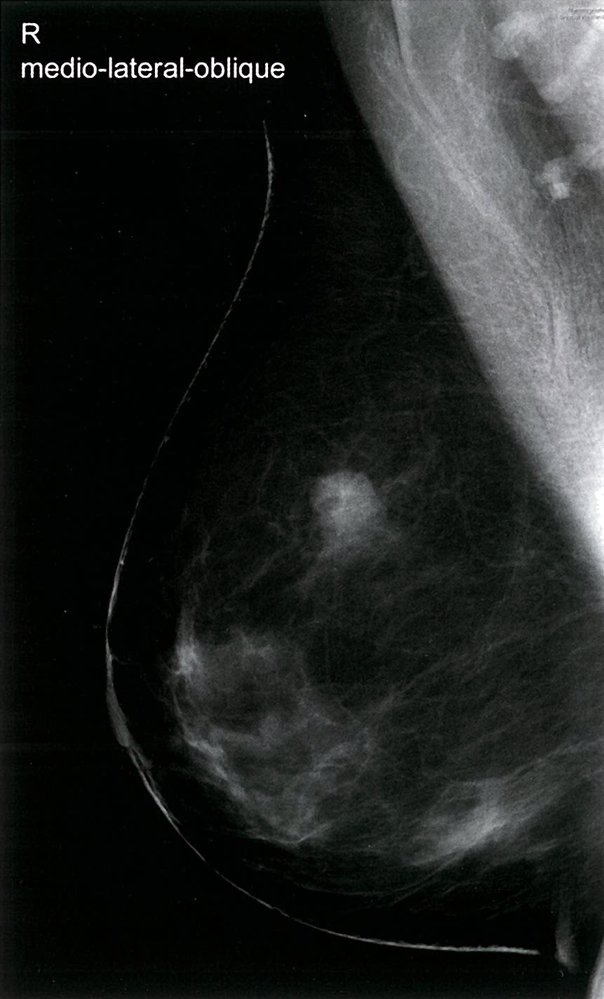

Screening mammography

• Mammography performed in asymptomatic individuals for early identification and management of breast cancer.

• Typically limited to bilateral craniocaudal and mediolateral oblique views of the breast.

• Additional views or digital breast tomosynthesis may be performed to improve visualization of breast tissue if necessary.

Diagnostic mammography

• Mammography performed to evaluate concerning breast symptoms (e.g., breast mass, focal pain, nipple discharge) or to further evaluate abnormalities detected on screening mammography or breast MRI.

• In addition to craniocaudal and mediolateral views, supplemental views (e.g., spot compression with magnification) with or without digital breast tomosynthesis may be performed to improve visualization of breast abnormalities.